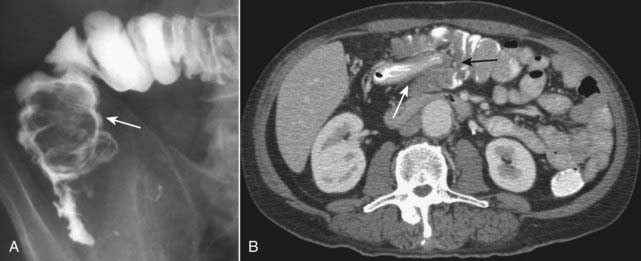

image

Figure 18-18 Intussusception, barium enema, and CT scan.

A, When one loop of bowel prolapses inside the loop immediately distal to it, the resultant obstruction produces a coiled-spring appearance on barium enema examination as two loops of bowel are superimposed on one another (solid white arrow). B, In another patient with an intussusception, a loop of large bowel (solid white arrow) is seen prolapsing into the loop distal to it (solid black arrow) producing a filling defect and obstructing the lumen.